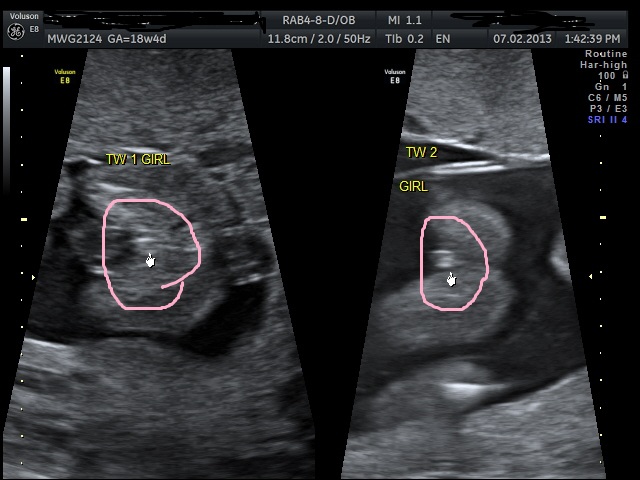

mapel congrats i'm praying for twin girls! so perfect i'm sure first 6 months will be manic but two of each how perfect so pleased for you x

girl